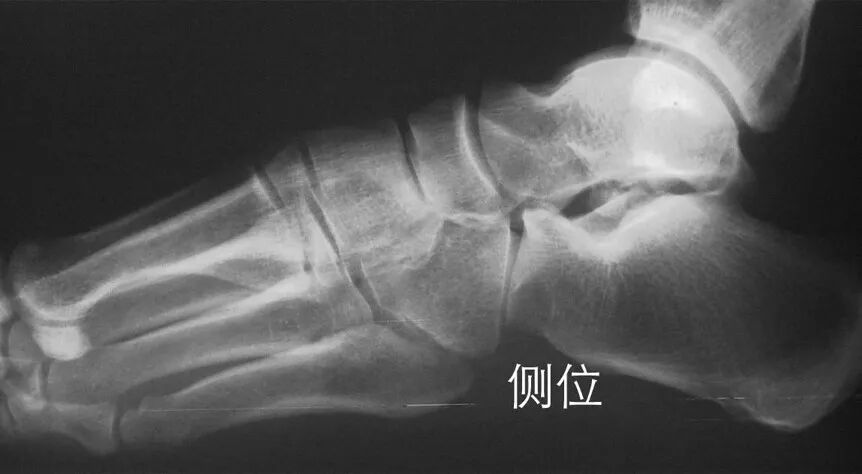

在足正位X线上,第1、2、3跖骨的内外侧缘分别和它相对应的楔骨的内外侧缘呈一直线排列;第一、二跖骨基底间隙和内中楔骨间隙相等。

30°斜位上:1、第四跖骨内侧缘和骰骨内侧缘连续成一条直线2、第三跖骨内侧缘和外侧楔骨内侧缘连续成一条直线3、第二、三跖骨基底间隙和内、中楔骨间隙相等。

侧位上,跖骨不超过相应楔骨背侧缘。从远端的跖骨经过跖跗关节到近端的跗骨,应该是一条不间断的连线

2005年Pearse等提出“ABC”的方法来阅读足部X 线片, 以减少中、前足的漏诊。 A ( alignment)检查跖骨与相应楔骨的对应线 B ( bone)检查每一块骨的轮廓 C ( congruity )检查整体一致吻合, 在正位片上观察内柱, 在斜位片上观察中、外柱。侧位片的常规检查可发现Lisfranc关节矢状面的半脱位及撕脱性骨折

特殊放射学检查应力位摄片:评价跖跗关节的稳定性负重位摄片:评价足的纵弓的稳定性,以及明确第1跖骨间隙的增宽 外侧斜位:诊断细微的第1跖骨间隙的增宽CT 扫描:诊断不明显的跖跗关节半脱位对照位摄片:明确细微的损伤